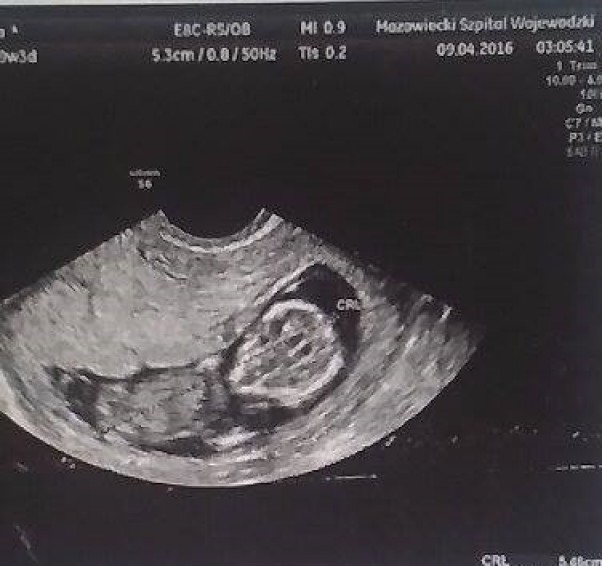

Zona moja chora biedna...zapalenie pęcherza złapała...ale musieli sprawdzić czy z Dzieckiem ok i na izbie zrobili nam usg. Wszystko z Dzidzią ok ale ona bardzo cierpi wiec zostajemy na jakiś czas w szpitalu...